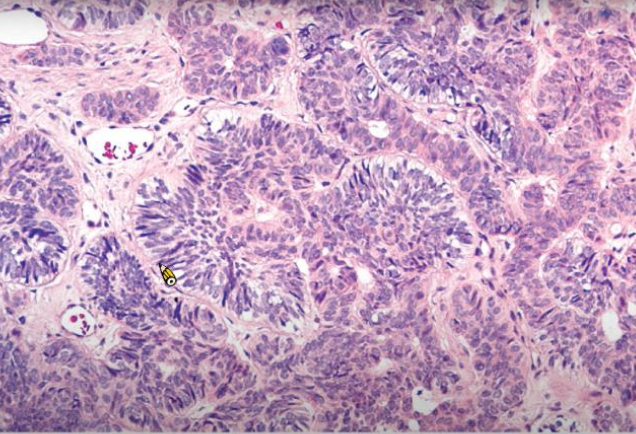

Clear cell odontogenic carcinoma biphasic 一堆 Clear cell, 一堆 Glycogen - -

• Clear cell

• 嗜酸多邊形上皮 (eosinophilic polygonal epithelial cells)

alt text

monophasic - - -

• 只有 Clear cell

• 均質 hyalinized CT

ameloblastoma-like - - -

• 最外圈 Clear cell 反極